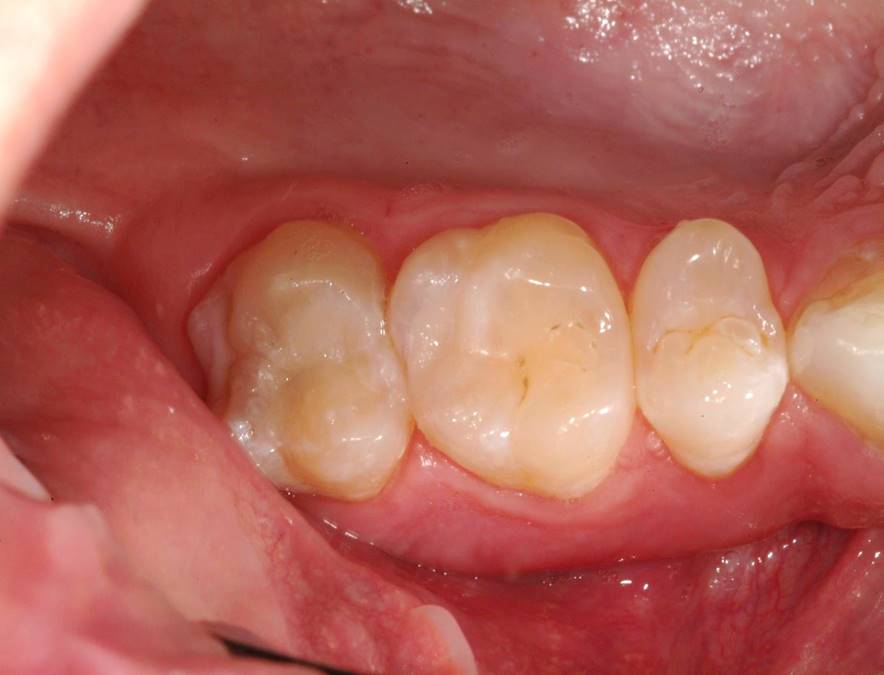

Fig 6. The amalgam restorations were thoroughly removed and the cavities prepared, after which caries indicator was applied to ensure the presence of only healthy, caries-free tooth structure.

Figure 6